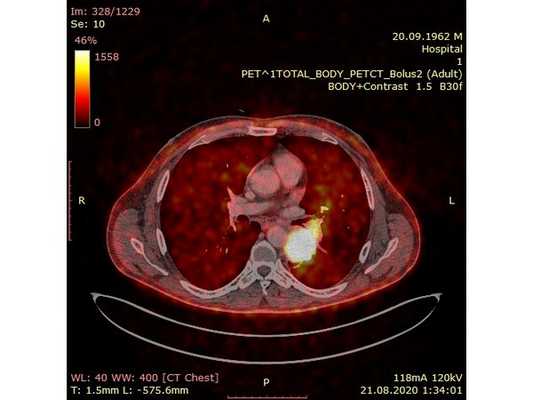

Чтобы провести первичное стадирование опухоли, пациенту проведена позитронно-эмиссионная томография в сочетании с компьютерной томографией (ПЭТ-КТ). По данным исследования, выявлена метаболически активная опухоль в корне левого лёгкого с бугристыми контурами размерами 41 х 43 мм. В толще опухоли проходят нижнедолевой бронх и бронх 6-го сегмента левого лёгкого, просветы бронхов значительно сужены. Нижняя доля левого лёгкого уменьшена в размерах за счёт того, что сегменты 6, 9 и 10 субтотально (частично) инфильтрированы и безвоздушны. Лимфатические узлы корня лёгкого и средостения не увеличены в размерах и не накапливают радиофармпрепарат (РФП), который был введён пациенту перед обследованием внутривенно. Других очаговых образований и очагов гиперметаболизма в организме не обнаружено.

При этом отмечено, что опухоль распространяется в средостение по нижней стенке левого главного бронха и широко прилежит к нижнегрудному отделу аорты (по заключению специалиста ПЭТ-КТ — имеется инвазия опухоли в ткани средостения и возможное врастание в стенку аорты). При самостоятельном пересмотре изображений отмечено, что "опухолевая" ткань, которая распространяется по нижней стенке левого главного бронха в средостение, не накапливает РФП (т. е. не является злокачественной), а стенка аорты в области "инвазии" опухоли имеет ровный чёткий контур и адвентициальную границу, что также свидетельствует об отсутствии онкологического процесса в этой области.